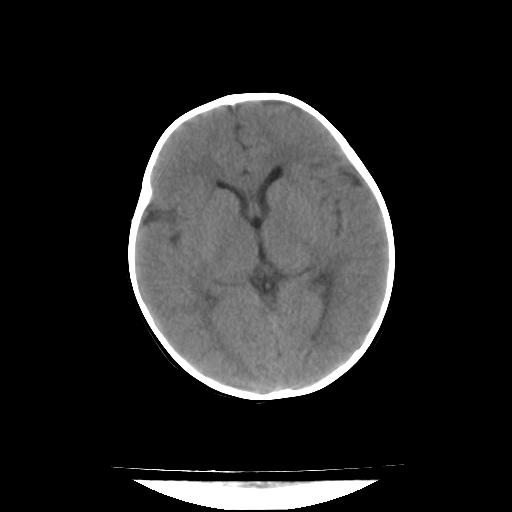

女,10个月,头外伤三天,伤后爱哭闹,吃奶少,睡觉不踏实。

1)左侧颞极蛛网膜囊肿。2)第四脑室出血?

1、左侧颞极蛛网膜囊肿;2、第四脑室出血?3、右侧顶叶脑裂畸形伴灰质异位?

1)左侧颞极蛛网膜囊肿。2)第四脑室内高密度影,性质待定。